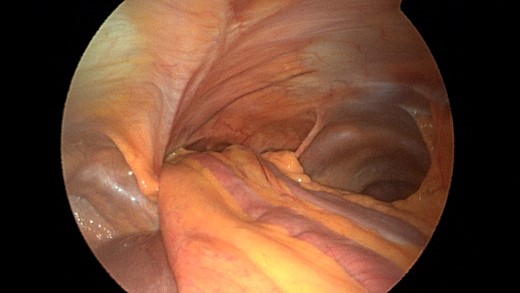

Laparoscopic view of the retroxyphoid defect in the diaphragm demonstrating multiple loops of small bowel and colon.

Closer view of the retroxyphoid defect demonstrating its large size with the edge of the diaphragm unattached to the undersurface of the abdominal wall.